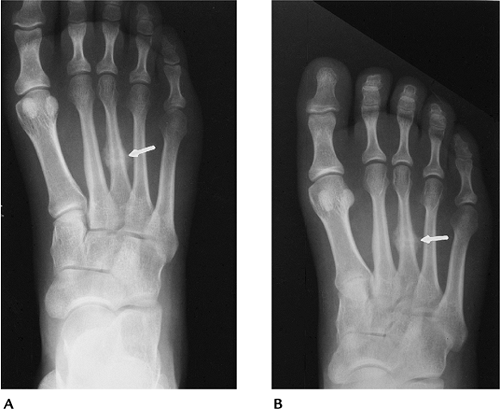

Fractures/Dislocations: Forefoot Injuries—Fifth Metatarsal Fractures

-

Fractures of the fifth metatarsal base are common in children and adults.

Fractures are categorized as proximal or distal.

Proximal fractures are divided into three zones (Fig. 6-34).

Zone 1, avulsion fractures; Zone 2, Jone’s fractures caused by forefoot

adduction; Zone 3, typically athletic stress fractures. -

Distal fractures (Dancer’s fracture) are usually the result of a direct blow.

Treatment of fractures in Zone 1 and distal fractures is conservative. Fractures in Zones 2 and 3 may require internal fixation.

![]() |

FIGURE 6-34 Oblique radiograph demonstrating the three zones of the proximal fifth metatarsal. There is an ununited Jone’s fracture (arrow) in Zone 2.

FIGURE 6-35 Avulsion fracture of the fifth metatarsal base in Zone 1 (arrow).